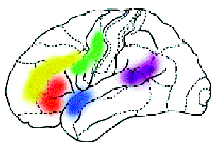

Область, отвечающая за определение грамматических характеристик слова Зона, активная при необходимости использования кратковременной памяти Зоны речевой моторики Зоны первичной обработки цвета Зоны, участвующие в обработке синтаксической структуры предложений Зона орфографической обработки слов Область, участвующая в сознательной и непроизвольной обработке смысла слов Области, предположительно управляющие подавлением обработки речевых признаков в задаче на обработку физического признака слова, например цвета |

Найдены микроучастки мозга, которые отвечают за счёт, за различение конкретных и абстрактных слов. Показаны различия в работе нейронов при восприятии слова родного языка (чашка), квазислова родного языка (чохна) и слова иностранного (вахт — время по-азербайджански).

А теперь представьте, что человек выполняет какое-то сложное задание, требующее от него знания правил орфографии или логического мышления. При этом у него наиболее активно работают нервные клетки в области мозга, „ответственной“ именно за эти навыки. Усиление работы нервных клеток можно зарегистрировать с помощью ПЭТ по увеличению кровотока в активизированной зоне. Таким образом удалось определить, какие области мозга „отвечают“ за синтаксис, орфографию, смысл речи и за решение других задач. Например, известны зоны, которые активизируются при предъявлении слов, неважно, надо их читать или нет. Есть и зоны, которые активизируются, чтобы „ничего не делать“, когда, например, человек слушает рассказ, но не слышит его, следя за чем-то другим.

Исследования,

проведённые в последние годы в Институте

мозга человека Российской академии

наук, позволили определить, какие

области мозга отвечают за осмысление

различных особенностей воспринимаемой

человеком речи: за грамматику, синтаксис,

орфографию и другие.